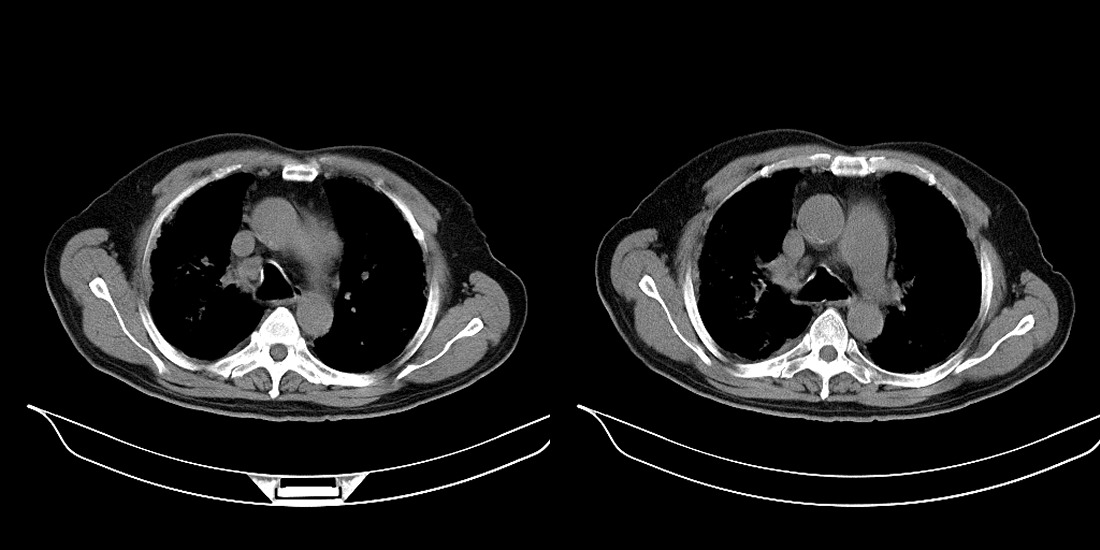

以下是引用zsl6918在2008-2-14 12:15:00的发言:[br]慢支并感染,肺气肿,肺间质纤维化,肺动脉高压。

以下是引用liuyue在2008-2-14 17:25:00的发言:[br]慢支并感染,肺气肿,肺间质纤维化,肺动脉高压 .肺大泡.[br]

以下是引用随光逐影在2008-2-15 11:10:00的发言:[br]1)慢性支气管炎并肺部感染。2)肺间质纤维化。3)肺气肿(多发性肺大泡形成)。4)肺动脉高压。